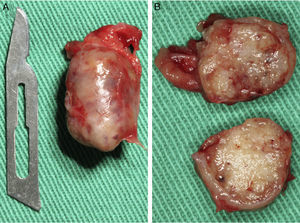

Casos clínicosCaso 1Paciente do sexo masculino, 68 anos de idade, leucoderma, procurou a Clínica de Estomatologia do Departamento de Odontologia da Pontifícia Universidade Católica de Minas Gerais (PUC Minas) queixando‐se de aumento de volume no palato, com tempo de evolução de 2 anos e discreta sintomatologia dolorosa. A anamnese não revelou alterações sistémicas. Ao exame clínico extraoral não foram observadas alterações. O exame clínico intraoral mostrou lesão nodular, pediculada, de consistência firme, localizada no palato duro do lado direito, entre os pré‐molares superiores e a rafe palatina, medindo aproximadamente 2cm na sua maior extensão. Foi realizada uma radiografia oclusal de maxila que não mostrou alterações ósseas. As hipóteses diagnósticas de neoplasia de glândula salivar e neoplasia mesenquimal benigna foram consideradas. Foi realizada biópsia incisional com diagnóstico anatomopatológico de adenoma pleomórfico. O tratamento proposto para a lesão foi a remoção cirúrgica conservadora. Paciente retornou após 4 semanas exibindo, ao exame intraoral, ulcerações na mucosa que recobria a lesão (fig. 1). Inicialmente, foi realizada anestesia local por meio da técnica supraperiosteal para bloqueio de ramos do nervo palatino maior, com cloridrato de lidocaína 2% e epinefrina 1:100.000 (ALPHACAINE 100®, DFL, Rio de Janeiro, Brasil). Em seguida, foi realizada incisão na base da lesão com bisturi lâmina 15 (Solidor, São Paulo, Brasil) e, após o descolamento do retalho mucoso palatino, a lesão foi exposta e removida (fig. 2). Foi realizada limpeza da ferida cirúrgica e sutura com fio seda Ethicon™ 4.0 (Johnson & Johnson, São Paulo, Brasil) (fig. 3). A lesão excisada (fig. 4) foi fixada em solução de formaldeído a 10% e enviada para exame anatomopatológico no Laboratório de Patologia Bucal da PUC Minas.

Paciente do sexo feminino, 31 anos de idade, leucoderma, foi encaminhada pelo cirurgião‐dentista à Clínica de Estomatologia do Departamento de Odontologia da PUC Minas para avaliação de lesão nodular no palato duro com diagnóstico histopatológico de adenoma pleomórfico, obtido por meio de biópsia incisional. Durante a anamnese, a paciente relatou a evolução da lesão há 4 anos com característica assintomática. Relatou estar no sexto mês de gestação e não apresentava outras alterações sistémicas. O exame extraoral mostrou ausência de alterações. Ao exame intraoral, observou‐se um aumento de volume bem delimitado no palato duro do lado direito, de consistência firme e coloração semelhante à da mucosa normal, medindo aproximadamente 2,5cm, exibindo pequena área de ulceração no local da realização da biópsia incisional (fig. 9). O exame radiográfico não mostrou alterações. O tratamento proposto foi a remoção cirúrgica conservadora e confecção de placa palatina em acrílico com grampos retentores para minimizar o desconforto pós‐operatório. Foi realizada anestesia local com lidocaína 2% e epinefrina 1:100.000 (ALPHACAINE 100®, DFL, Rio de Janeiro, Brasil), seguida de incisão semilunar com bisturi lâmina 15 (Solidor, São Paulo, Brasil) e rebatimento do retalho mucoso. Como a lesão se apresentava encapsulada, foi possível destacá‐la da mucosa suprajacente com facilidade (fig. 10). O retalho foi reposicionado por meio de pontos isolados (fig. 11) e a lesão (fig. 12) foi fixada em formaldeído a 10% para realização de exame anatomopatológico no Laboratório de Patologia Bucal da PUC Minas. Em seguida, foi colocada a placa de acrílico (fig. 13) para proteção da região operada e controlo da sintomatologia dolorosa.